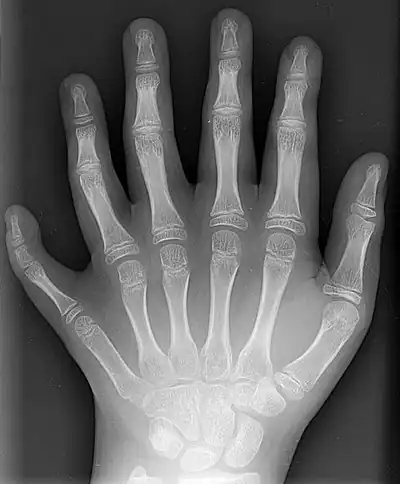

Humans normally have five digits on each extremity. Each digit is formed by several bones called phalanges, surrounded by soft tissue. Human fingers normally have a nail at the distal phalanx. The phenomenon of polydactyly occurs when extra digits are present; fewer digits than normal are also possible, for instance in ectrodactyly. Whether such a mutation can be surgically corrected, and whether such correction is indicated, is case-dependent.[1] For instance the former chess world champion Mikhail Tal lived all his life with only three right-hand fingers.